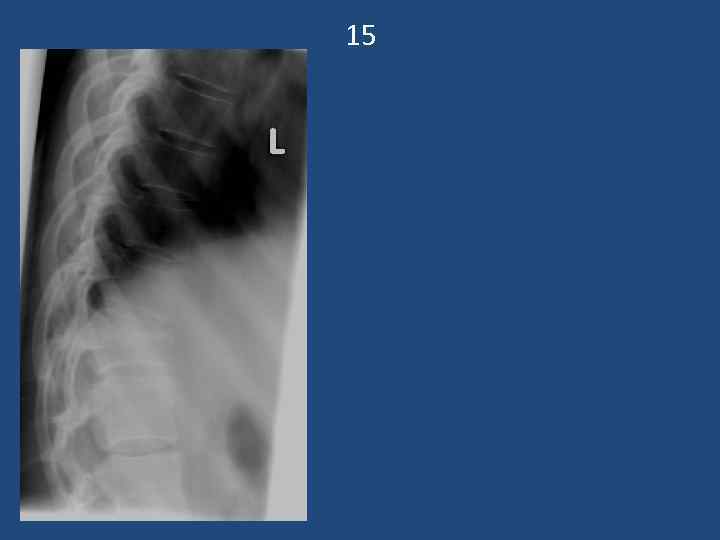

15